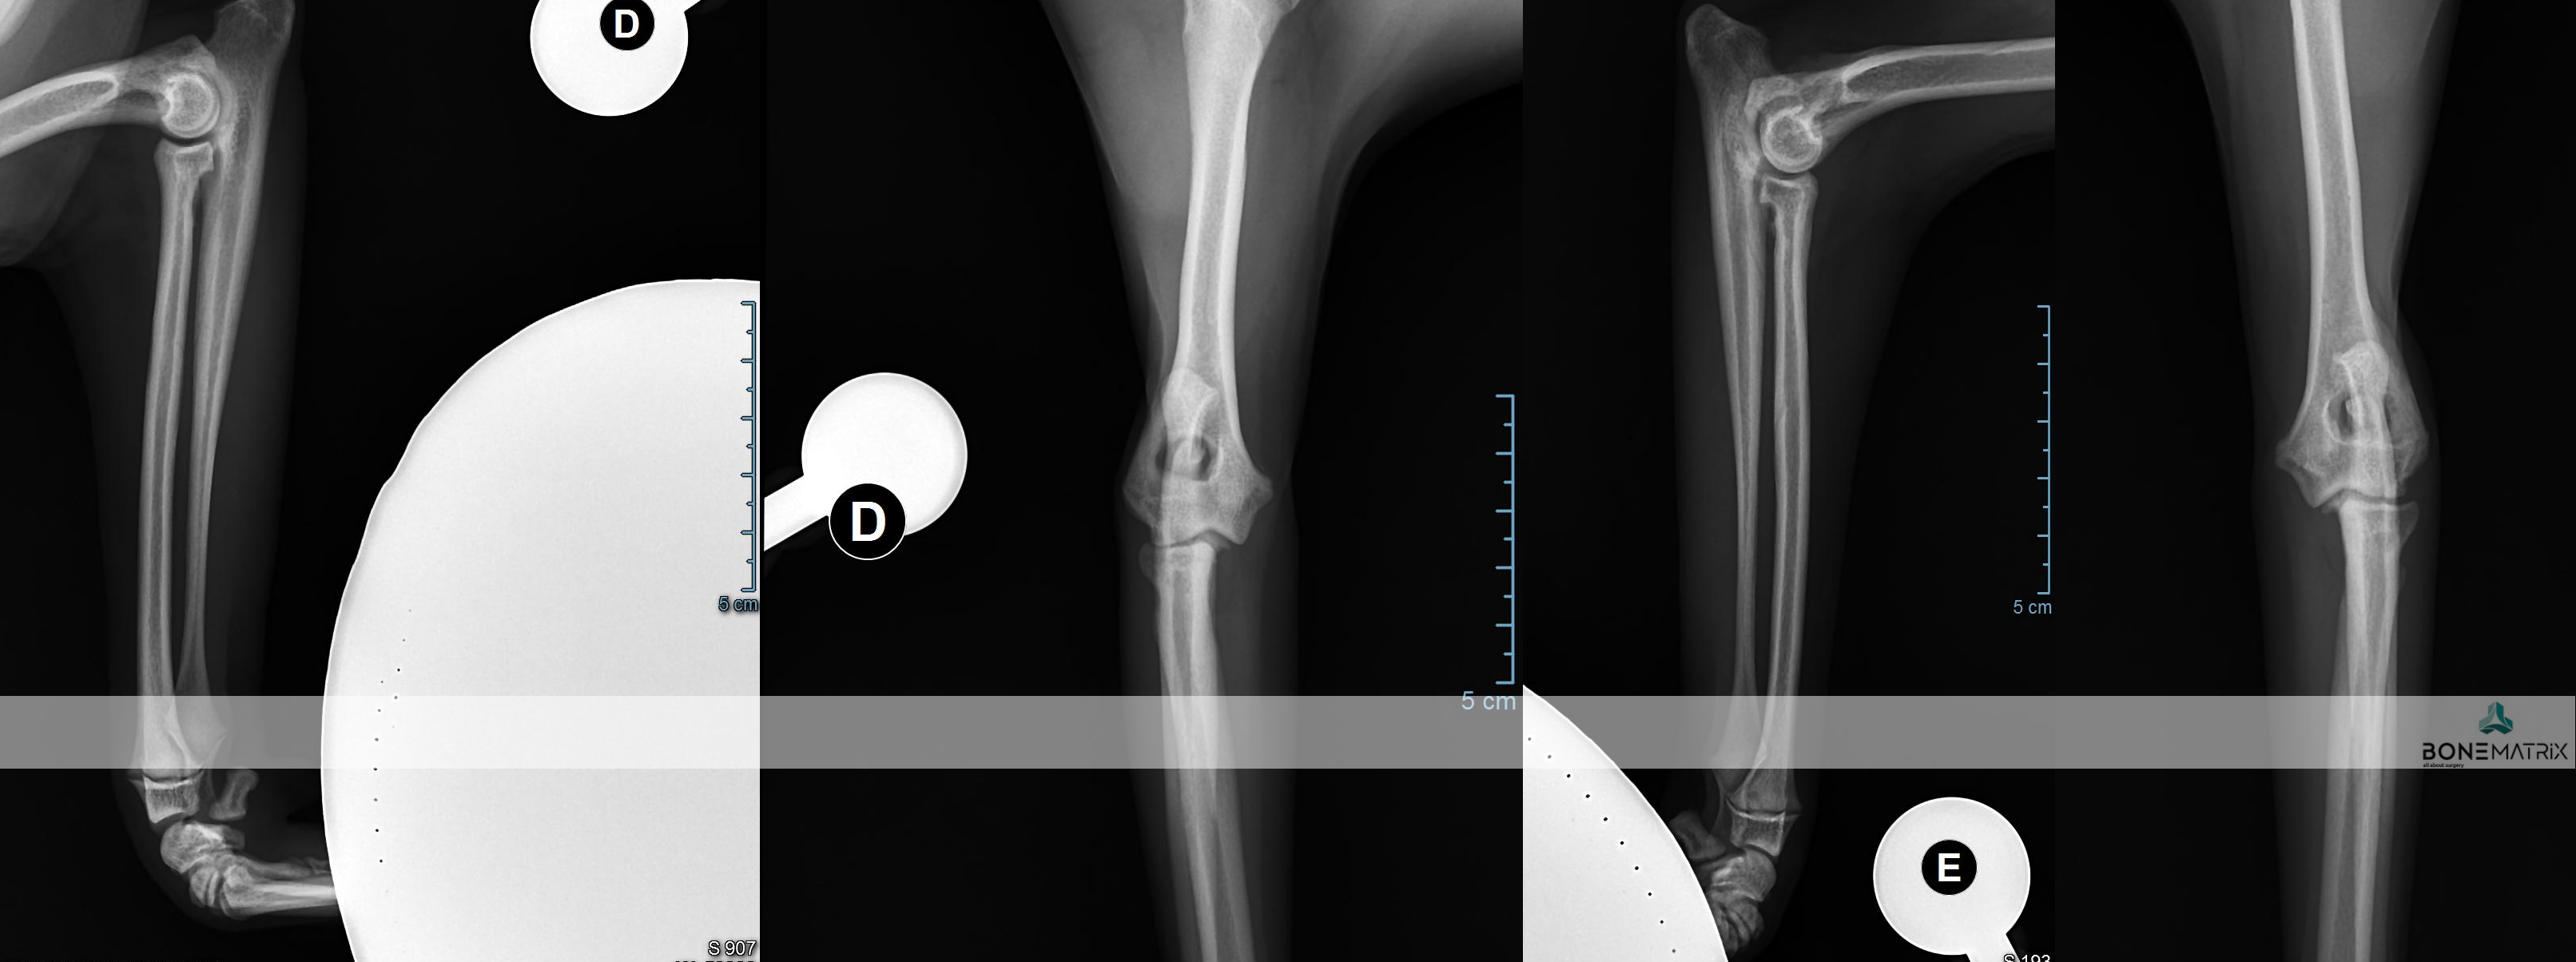

A displasia de cotovelo é uma doença de desenvolvimento caracterizada pela incongruência do cotovelo.

Dada a componente genética, frequentemente envolvida no decorrer deste processo, a patologia apresenta-se por norma bilateralmente, podendo assumir gravidade diferente em ambos os cotovelos.

Esta patologia quando unilateral, por norma, está relacionada com um evento traumático, ocorrido durante o crescimento do animal.

A displasia de cotovelo pode assumir várias apresentações, entre elas, a não união do processo ancóneo, a fragmentação do processo coronóide, a osteocondrite dissecante, doença do compartimento medial e a incongruência per si.

Todas estas apresentações tem em comum contribuírem para o desenvolvimento acelerado de um quadro de osteoartrite a nível intra-articular.

Como é criada esta incongruência?

A articulação do cotovelo é constituída por 3 ossos, o rádio, a ulna e o úmero.

A incongruência do rádio resulta na apresentação deste osso mais curto que a ulna. Isto resulta num excesso de pressão sobre regiões da ulna - resulta com frequência na fragmentação do processo coronóide.

Quando a apresentação contrária ocorre, ou seja, o rádio apresenta-se mais elevado que a ulna, é exercida demasiada pressão sobre o processo ancóneo - resultando com frequência na não união do processo ancóneo.

Quando a incongruência envolve o úmero outras lesões podem ser desenvolvidas que envolvem o desalinhamento articular entre o úmero e a ulna.

As incongruências descritas também podem ser consequência de um encerramento precoce traumático das placas de crescimento destes ossos (locais responsáveis pelo crescimento longitudinal dos ossos).

A apresentação desta patologia em fases iniciais apresenta, com frequência, sinais subtis, daí a necessidade de realização de despiste de displasia de anca durante o crescimento do animal (idealmente 5 meses) para que a doença possa ser detetada antes que ocorra um desenvolvimento significativo de lesões de osteoartrite a nível intra-articular.

O diagnóstico pode ser realizado por meio de estudo radiográfico.

Contudo são indicadas técnicas de imagem avançada (tomografia axial computorizada) ou artroscopia para a realização do diagnóstico final e definição de abordagem terapêutica.